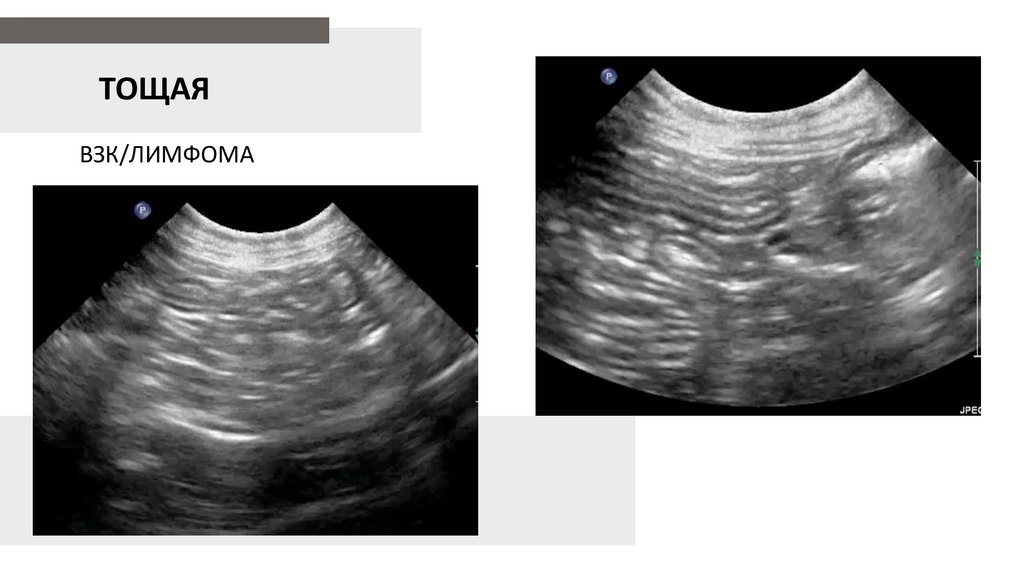

ТОЩАЯ

ВЗК/ЛИМФОМА